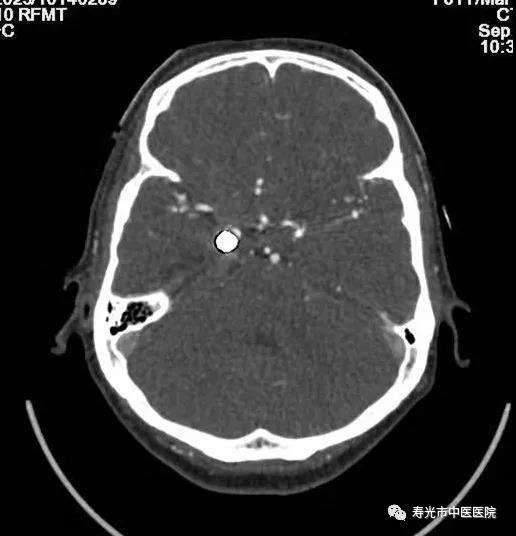

CT下冠脉CTA 3D成像

这台CT的领先之处还有很多,去伪影技术更是极大帮助了医生进行治疗。有一位患者,曾经做过脑动脉瘤手术,后来又出现症状,需要再进行脑血管成像。可是患者脑部已经置入了金属,使用普通CT扫描时,金属会带来反射,拍出来的照片一片模糊根本看不清楚病灶。他慕名来到寿光市中医医院求助,在这里,医生利用这台CT的去伪影技术,对他进行了扫描,扫描成像非常清楚。这成了该设备去伪影技术的一个经典病例,美国GE公司的培训师特意将影像搜集去,在全世界范围进行了分享。

CT去伪影扫描效果对比